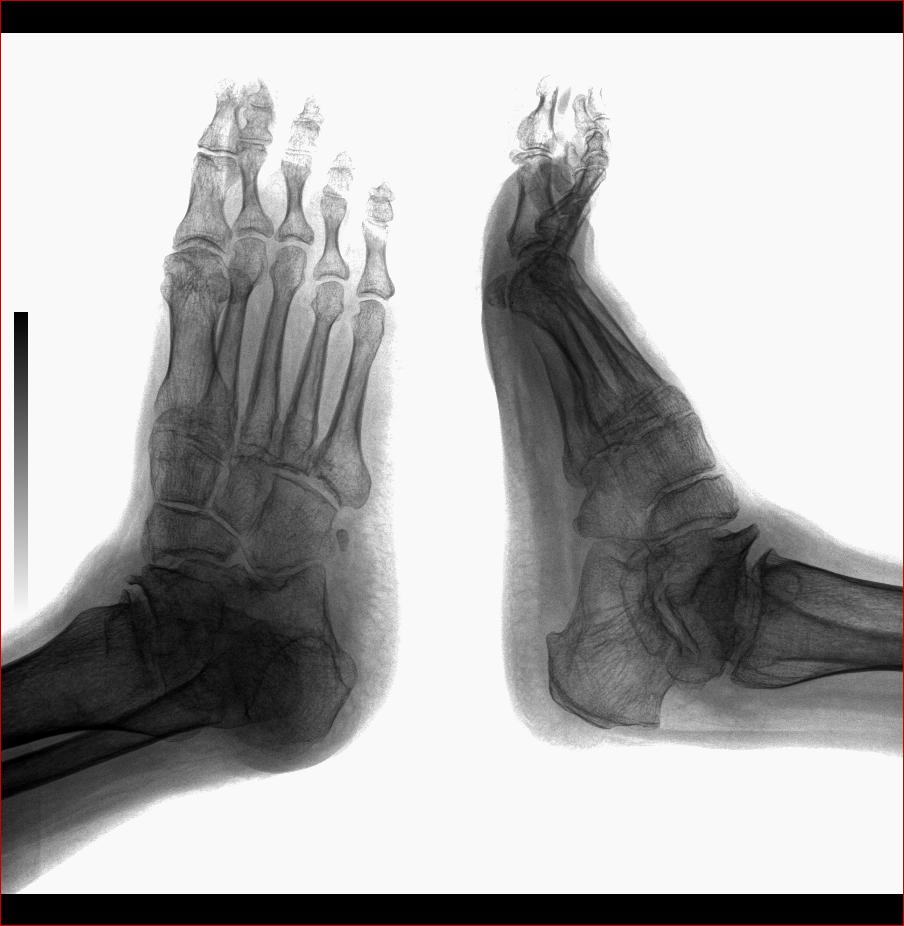

以下是引用杏林古木在2008-4-26 18:31:00的发言:[br]大骨节病。

以下是引用yangwq在2008-4-26 21:52:00的发言:[br]1 痛风 2 距骨缺血性改变 3退变

以下是引用yangyudong333在2008-4-27 6:28:00的发言:[br]跟骨短,矩骨扁,符合大骨节病

以下是引用光影相伴在2008-4-26 18:32:00的发言:[br]考虑:大骨节病。